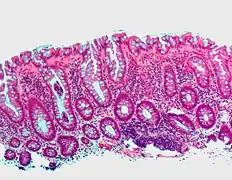

Hyperplastic polyp

Most hyperplastic polyps are found in the distal colon and rectum.[18] They have no malignant potential,[18] which means that they are no more likely than normal tissue to eventually become a cancer.

Microvesicular hyperplastic polyp. H&E stain.